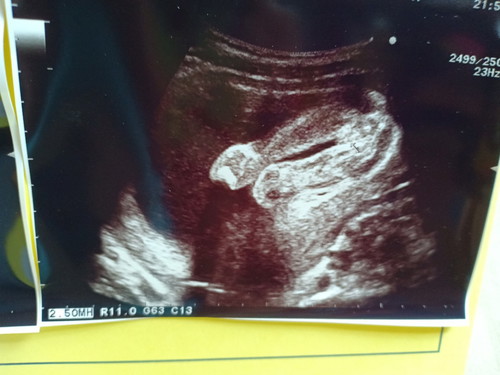

เพศไหนคะเนี้ยยย

น่าจะ ญ คะแม่ ในรูป เราก็อยากได้ชายลูกคนแรกแต่ได้ ญ เหมือนกันคะ ยังไงจะเพศไหนก็รักเนาะ555ลูกเรา

น่าจะผู้หญิงน่ะค่ะ บ้านนี้ผู้ชายค่ะ จะมีจู๋ยื่นออกมาตามรูปเลยค่ะ 😋😋😋😋😋😋😋😋😋😋😋

น่าจะหญิงนะคะ ถ้าผู้ชายจะมีติ่งยื่นออกมาชัดเจนเหมือนของบ้านนี้จ้า

ขอบคุณค่ะ ไปซาวด์ตอน12วีคยังไม่รู้เลยค่ะ ตอนนี้14วีคแล้ว รอลุ้นมากเลยค่ะ😊